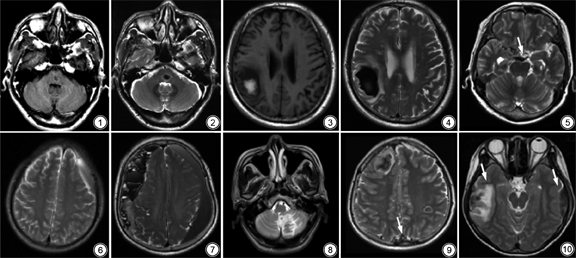

正常颅内T2WI低信号结构包括硬脑膜、颅神经、血管、灰质核团。颅内血管因流空效应,表现为T2WI低信号,尤以大脑中动脉M1段、基底动脉、颈内动脉虹吸段明显。灰质核团包括苍白球、壳核、黑质、红核、齿状核等结构,它们均富含铁,可缩短T2弛豫时间[1],因而T2WI表现为低信号,且苍白球及壳核铁沉积随年龄增长而增加。

血液溢出血管外后,随着氧的消耗,血红蛋白转变为脱氧血红蛋白,为急性期,T1WI和T2WI均为低信号,以T2WI为明显。随着氧的进一步消耗,脱氧血红蛋白转变为高铁血红蛋白,进入亚急性早期,此时红细胞膜仍完整,高铁血红蛋白位于红细胞内,在T1WI上呈高信号,T2WI上呈明显低信号[2]。

颅内出血根据部位分为脑内血肿、蛛网膜下腔出血、硬膜下血肿和硬膜外血肿。引起脑内血肿的病因有很多,包括高血压、血管畸形、凝血功能障碍、外伤、脑淀粉样血管病等,结合临床有助于病因的确定。血肿周围脑组织水肿,血肿可破入脑室,导致脑室铸形或出现血液平(图1, 2, 3, 4)。

蛛网膜下腔出血的病因包括外伤、动脉瘤破裂、动静脉畸形等(图5)。血液位于脑沟裂、脑池内和(或)脑表面,血液聚积最明显的部位多为出血处。

硬膜外血肿和硬膜下血肿多有外伤史。前者指血液积聚于硬脑膜与颅骨之间,轴位图像上呈凸透镜形,不跨越颅缝(图6)。后者指血液积聚于硬脑膜与蛛网膜之间,轴位图像上呈新月形,可跨越颅缝[3],不延伸至脑沟裂内;血肿机化后牵拉血管致其破裂再出血,则可形成液平(图7);大脑镰和小脑幕旁的血肿为硬膜下血肿。

出血性梗死指缺血性卒中后,梗死区域或梗死血管分布区出现出血灶。发病原因目前认为与卒中后血脑屏障破坏和再灌注损伤有关[4]。其影像学表现分为三型:Ⅰ型,梗死区域内可见散在小点状出血,无占位效应;Ⅱ型,多个融合的点状出血,无占位效应;Ⅲ型,血肿位于梗死组织内,体积≤30%梗死灶,并有轻微占位效应。T2WI上表现为高信号病灶内点状、斑片状低信号(图8)。

静脉性脑梗死是由于脑内静脉回流受阻引起引流区脑组织水肿、脑梗死和脑出血。临床表现主要为“雷击样”头痛、癫痫及颅内压增高症状[5]。MRI上多表现为皮层、皮层下多发或孤立性病灶,不符合动脉分布区域或大于一支动脉分布区域,可累及双侧基底节区及丘脑。静脉性出血性脑梗死T2WI上表现为高信号梗死灶内见斑片状低信号[6](图9)。发现静脉窦内血栓有助于诊断,在增强T1WI和磁共振静脉造影(magnetic resonance venography,MRV)上呈充盈缺损。

外伤可引起脑组织、软脑膜和血管撕裂,造成多发灶状出血。病灶多位于着力点及其附近,或其对冲部位[7]。早期多表现为大片状T1低信号、T2高信号水肿,其内伴有出血,信号取决于出血时期(图10)。而病变晚期由于病变区脑组织坏死、液化,瘢痕修复,软化灶形成,表现为T1低信号、T2高信号,FLAIR低信号周围可见高信号胶质增生,并伴相邻部位脑萎缩。